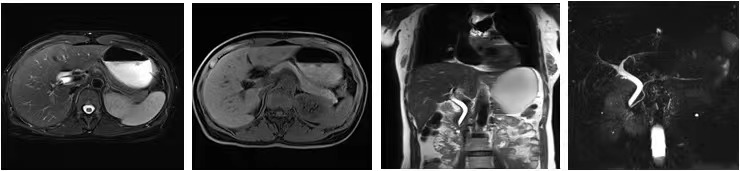

传统的磁共振成像对运动非常敏感。为了在体部获得有价值的诊断图像,扫描前都需要给患者佩戴呼吸门控装置,对患者进行呼吸训练,而且扫描中还要求患者多次屏气扫描。

而大量的重症患者、老年人和小孩都无法有效配合进行呼吸训练和屏气扫描,给成像带来了困难。

MAGNETOM Vida 3.0T磁共振配置了生命矩阵系统,这就使磁共振犹如具备生命一般,患者一躺上扫描床,磁共振就能真切地感受到患者解剖、呼吸、磁场等人体信息。在扫描过程中,无需患者刻意配合,无需佩戴任何呼吸门控装置,全程自由呼吸就可完成扫描,获得高质量的检查结果。

因此,重症患者、老年人和小孩患者群体也能舒适地进行扫描。